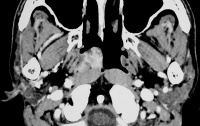

影像学诊断由三个方面组成:(1)X线检查;(2)CT检查;(3)MRI检查。

Bki7y.jpg

(七)鼻咽侧位片颅底片及CT检查 :每例患者均应常规作鼻咽侧位照片和颅底照片,疑及鼻旁窦中耳或其他部位有侵犯者,应同时作相应的摄片检查。有条件的单位应作CT扫描,了解局部扩展情况,特别需要掌握的是咽旁间隙的浸润范围,这对于确定临床分期以及制定治疗方案都极为重要。